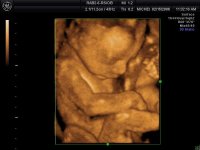

При необходимости вмешательств возможно использование новейших безболезненных методик с использованием лазера и криогенных технологий. Для ультразвуковых исследований применяют новейший ультразвуковой сканер с допплером и 3D | 4D визуализацией GE Healthcare пр-ва 2016 года (США) премиум-класса - это полностью цифровая универсальная цветная ультразвуковая система, построенная с использованием технологии TruScan - эксклюзивной технологии GE, обеспечивающей непревзойденное качество изображения, расширенные возможности обработки данных и высочайший уровень эргономики.

TruAccess - принципиально новый подход к получению УЗ изображений, основанный на обработке «сырых» данных. Использование этой технологии обеспечивает получение высококачественных изображений и предоставляет уникальные возможности их дальнейшей обработки.

SmartScan - новейшие программные алгоритмы для повышения продуктивности и обеспечения высочайшего качества обслуживания пациентов

ComfortScan - новый подход к созданию УЗ систем с высочайшим уровнем эргономики для обеспечения максимального комфорта пациента и пользователя, имеет постоянно-волновой допплер, цветовое картирование и функции 3D и 4D визуализации, с возможностью автоматического трехмерного сканирования в режиме реального времени с использованием специализированных датчиков, а также дуплексные и триплексные исследования. Благодаря множеству инноваций и инженерных решений, применённых в данной системе появилась возможность высокоточных, безвредных ультразвуковых исследований Premium-класса как при уточнении диагноза, так и при скринингах беременных на любом сроке с возможностью оценки кровотока, допплерографии, цервикометрии, 3D и 4D визуализации с возможностью первой записи Вашего малыша на диск или другой носитель.